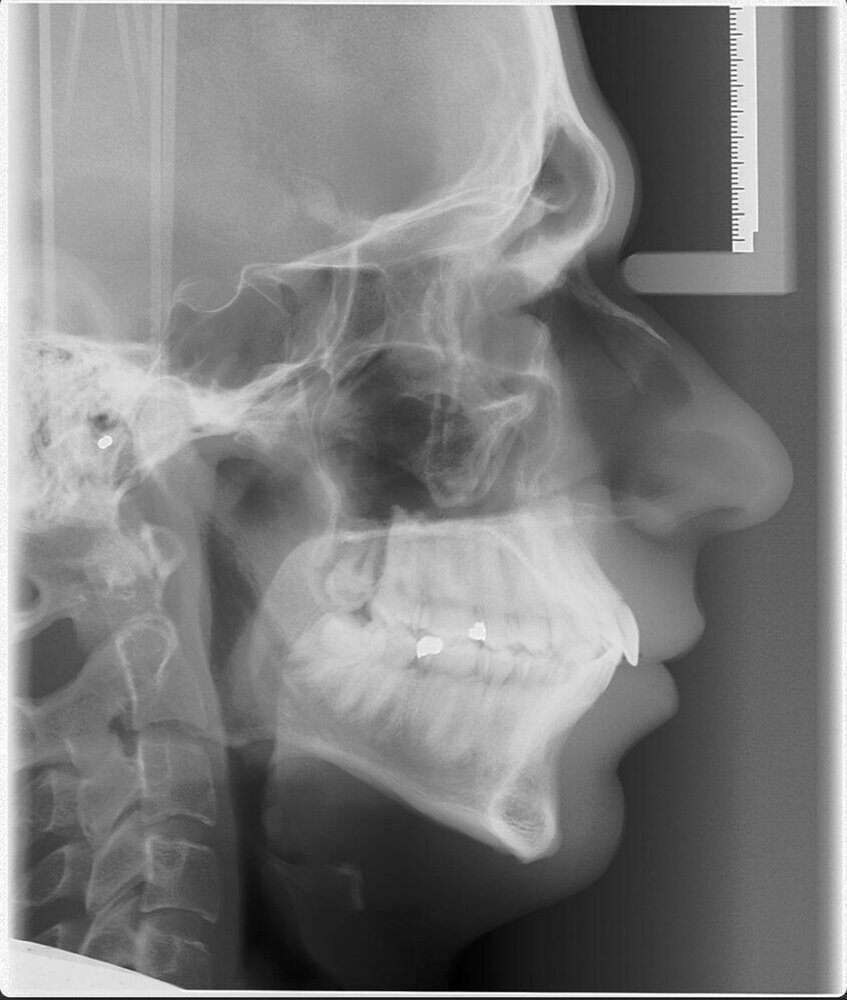

View attachment 950131

View attachment 950131